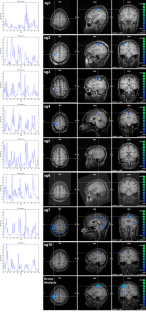

Fig. 1

Fig. 2

Fig. 3

Fig. 4

Fig. 5